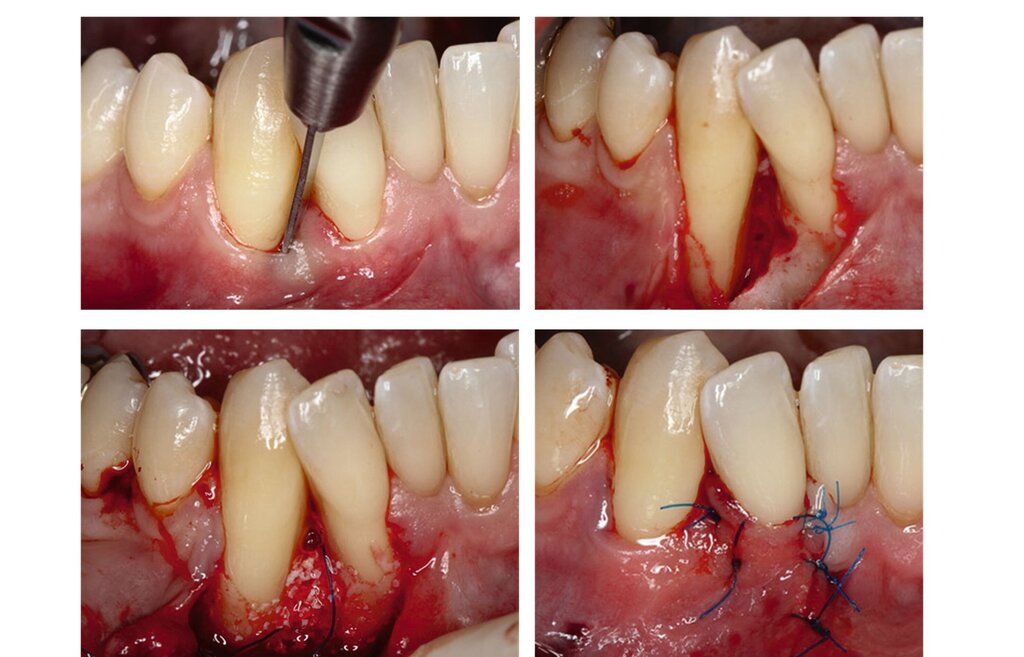

Die parodontale Regeneration ist eine gute Therapiemöglichkeit, um die Prognose von stark betroffenen Zähnen mit tiefen Resttaschen und Knochendefekten oder Furkationsdefekten zu verbessern. Der zusätzliche Nutzen für den Attachmentgewinn liegt bei durchschnittlich 1,34 mm und für die Reduktion der Sondierungstiefen bei 1,2 mm [Nibali et al., 2020]. Eine gute Plaquekontrolle wirkt sich dabei positiv auf das Heilungsergebnis aus und sollte deshalb die Basis für alle parodontalchirurgischen Maßnahmen sein [Rosling et al., 1976]. Auch Zähne mit Furkationsbefall sollten in die Parodontaltherapie einbezogen werden. Bei Furkationen von Unterkiefermolaren Grad II und Oberkiefermolaren mit bukkalem Furkationsbefund Grad II sollten regenerative parodontalchirurgische Maßnahmen in Betracht gezogen werden [Jepsen et al., 2020]. Zur Unterstützung der Regeneration von Knochentaschen oder Furkationsbefall Grad II stehen gut untersuchte Biomaterialien wie Membranen oder Schmelz-Matrix-Proteine mit oder ohne Zusatz von Knochenersatzmaterial zur Verfügung [Nibali et al., 2020]. Die Abbildungen 1 bis 3 zeigen einen Fall, bei dem durch eine regenerative Parodontalchirurgie die Prognose des Zahnes maßgeblich verbessert wurde.